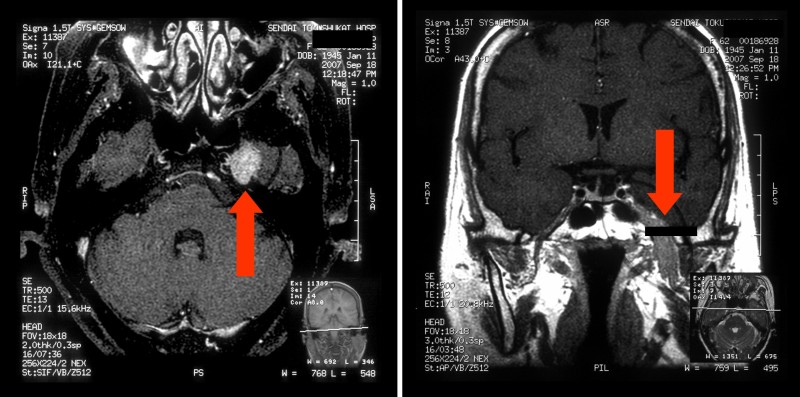

現病歴:2007年3月頃から舌下面左側と唇下左側のしびれ感が出現。同月、某病院口腔外科から同院内科を紹介され、MRIを撮影。

放射線科医師の読影では、古い梗塞病変のみと(図1、2)。

図1

図2

内科撮影のMRI(図6)にて、頭蓋底の左側卵円孔の拡大が認められ、この時点で腫瘍の存在したことが理解できた。